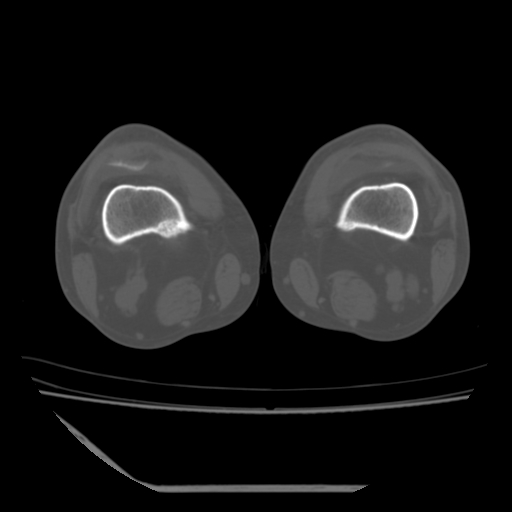

标题: CT13225:老年男性,左膝关节疼痛数月;请各位老师讨论。 [打印本页]

标题: CT13225:老年男性,左膝关节疼痛数月;请各位老师讨论。

骨质增生,骨性关节面硬化,关节积液,考虑退行性骨关节病

关节腔内少量积液,关节面退变。

双膝退变

骨质增生,骨性关节面硬化,关节间隙失常,关节积液,考虑退行性骨关节病.

骨质增生,骨性关节面硬化,关节积液,考虑退行性骨关节病。

这个病例诊断:退行性骨关节炎